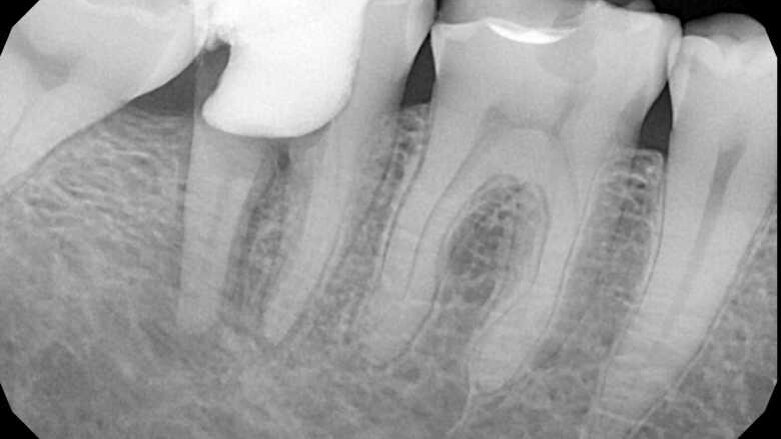

Pacijentkinja stara 41 godinu upućena je u našu ordinaciju radi ponovnog tretmana zuba 36. Nakon CBCT i RVG pregleda uočena je lezija nastala zbog neadekvatne opturacije i verovatno nepravilnog protokola irigacije. Kontrola infekcije nije uspela u ovom slučaju, međutim, zub je bio asimptomatičan. Odluka o ponovnom tretmanu je doneta i započeto je sprovođenje procedure.

SLIKA A